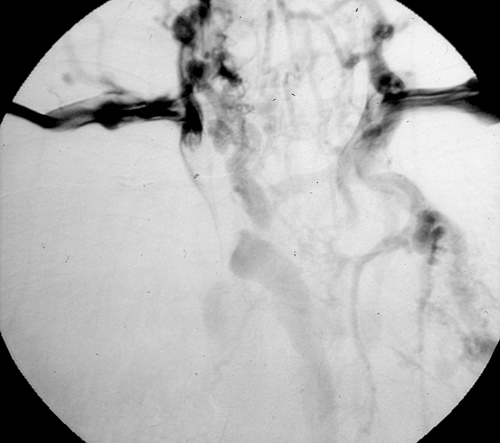

Figure 4

Figure 4. Superior vena cavography showing obstruction by a mediastinal tumor.

The preoperative work–up should always include total body CT scan for patients with lung cancer or tumors of the mediastinum. Other specific investigations should be tailored according to the histological diagnosis. Superior vena cavography should be performed when SVC invasion is suspected (Figure 4). Alternatively, magnetic resonance imaging can help to define the site and extension of the infiltration and the presence of thrombosis, and anatomical variations of the SVC system can be revealed. Echocardiography should be routinely included to rule out extension of a thrombus into the right atrium. Brain CT scan with contrast injection should always be performed for staging purposes (lung cancer) and also to rule out the presence of any brain disease that may be exacerbated by CNS edema during SVC clamping.